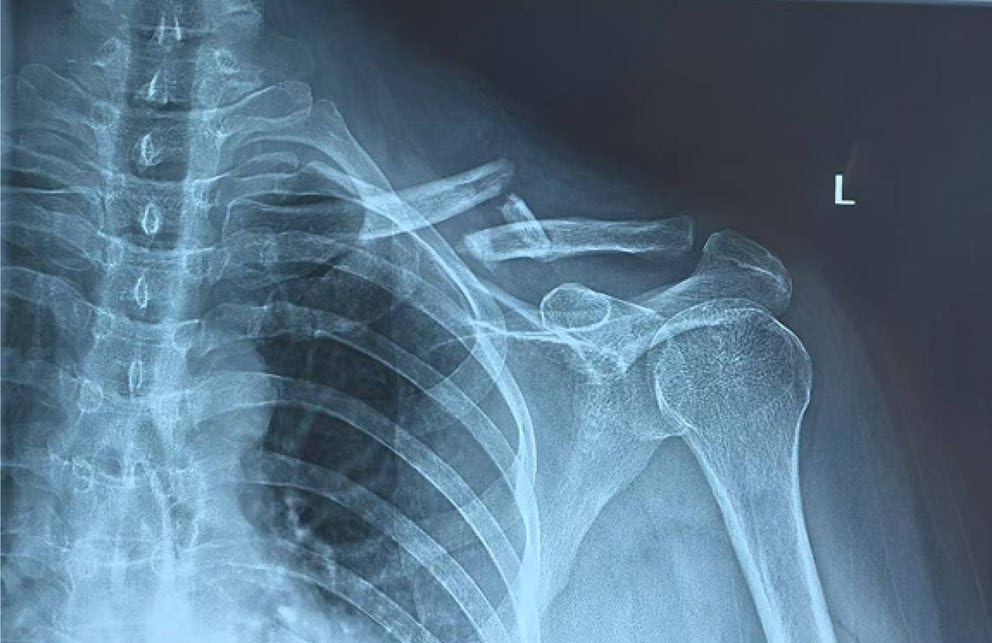

1、锁骨中段粉碎性骨折

1、锁骨MIPO:微创钢板接骨术。